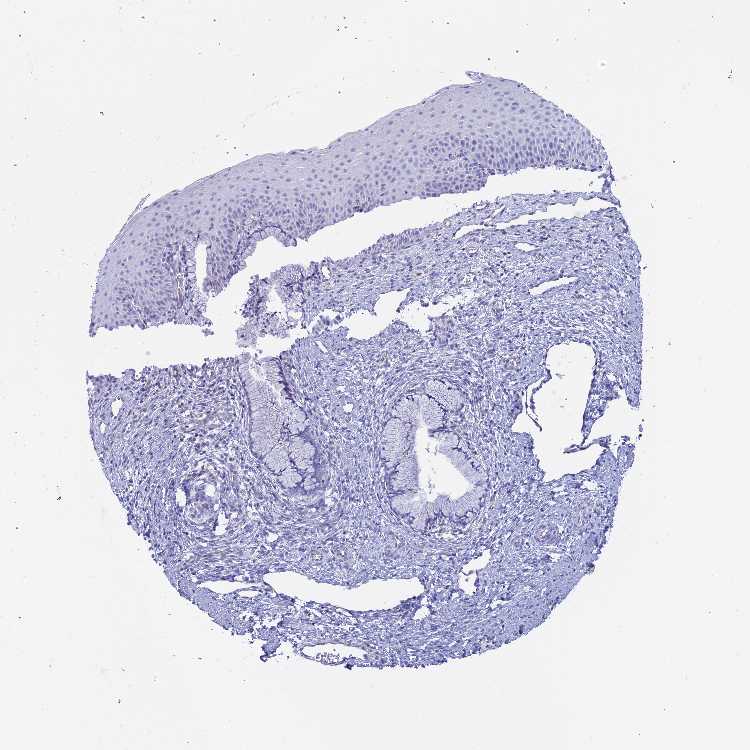

TISSUE PRIMARY DATA CERVIX Show tissue menu

Cervix

CERVIX - Antibody stainingi

Antibody staining in the annotated cell types in the current human tissue is reported as not detected, low, medium, or high, based on conventional immunohistochemistry profiling in selected tissues. This score is based on the combination of the staining intensity and fraction of stained cells.

Each image is clickable and will lead to virtual microscopy that enables deeper exploration of all samples and also displays staining intensity scores, fraction scores and subcellular localization as well as patient and tissue information for each sample.

Antibody HPA043381

Glandular cells Not detected

Squamous epithelial cells Not detected